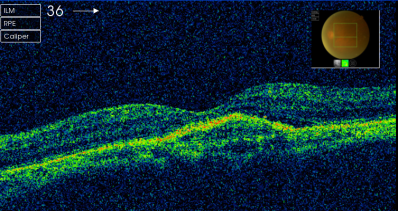

患者曹某,80岁,因双眼视力下降1年就诊。检查右眼视力0.3,左眼0.08,裂隙灯检查双眼晶体皮质混浊明显,散瞳后眼底检查见右眼黄斑区金箔样反光,左眼黄斑区中心凹反光消失。患者眼底荧光照影检查显示左眼黄斑区有血管荧光的渗漏,眼科光学相干断层扫描(OCT)检查显示右眼有黄斑前膜增生,左眼脉络膜新生血管膜(图片1)。诊断:左眼老年性黄斑变性(脉络膜新生血管),右眼黄斑前膜,双眼老年性白内障。患者于2013年3月行眼内注药(雷珠单抗)。3月后复诊左眼视力0.1,复查OCT示左眼视网膜新生血管膜消退(图片2),建议先行左眼白内障手术治疗。

图片2右眼黄斑前膜增生

专家点评:老年性黄斑变性是老年人视力下降的常见原因之一,它是由于视网膜光感细胞代谢产物逐渐堆积形成玻璃膜疣,刺激脉络膜组织形成新生血管。本病如果不经治疗,最终新生血管膜形成瘢痕,导致视力重度永久性丧失。以往针对老年性黄斑变性(脉络膜新生血管)主要做光动力学疗法(PDT),PDT主要起到稳定视力的作用,很少能够提高视力。抗VEGF药物(如雷珠单抗)的问世是此类疾病治疗革命性的突破。由于雷珠单抗是通过眼内注射给药,而且价格昂贵,目前国内多数给药方案为每月一次,连续三个月,然后根据病情发展情况决定是否需要追加给药。该患者因经济因素仅一次给药治疗,但已能观察到明显的脉络膜新生血管消退。由于患者白内障比较明显,故推荐先行白内障手术,术后仍需定期观察决定后续治疗方式。 |